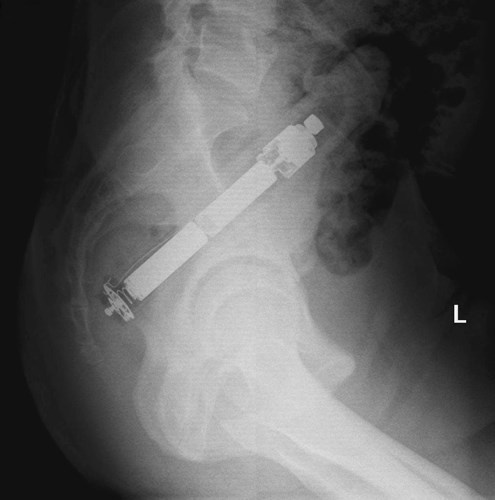

| Phim chụp của người đàn ông ở Malaysia bị mắc kẹt một chiếc chày khi anh ta đang nấu ăn. |